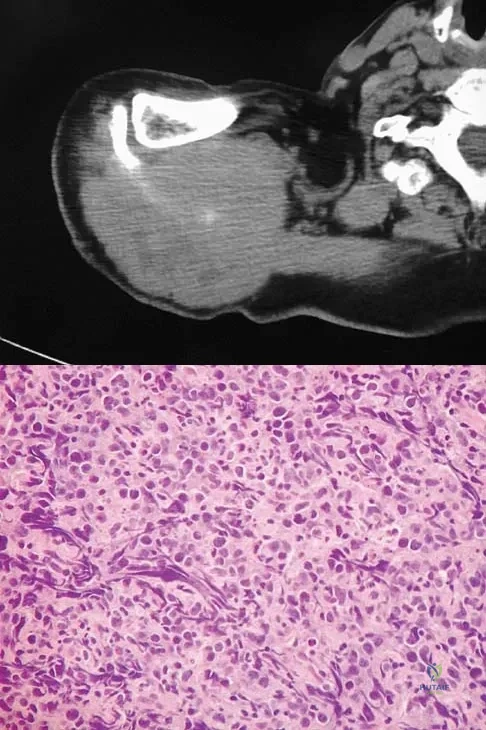

Question 46

A 65-year-old man has a painful right hip mass that has been growing for several years. A radiograph, CT scan, and photomicrograph are shown in Figures 56a through 56c. What is the most appropriate treatment?

Explanation